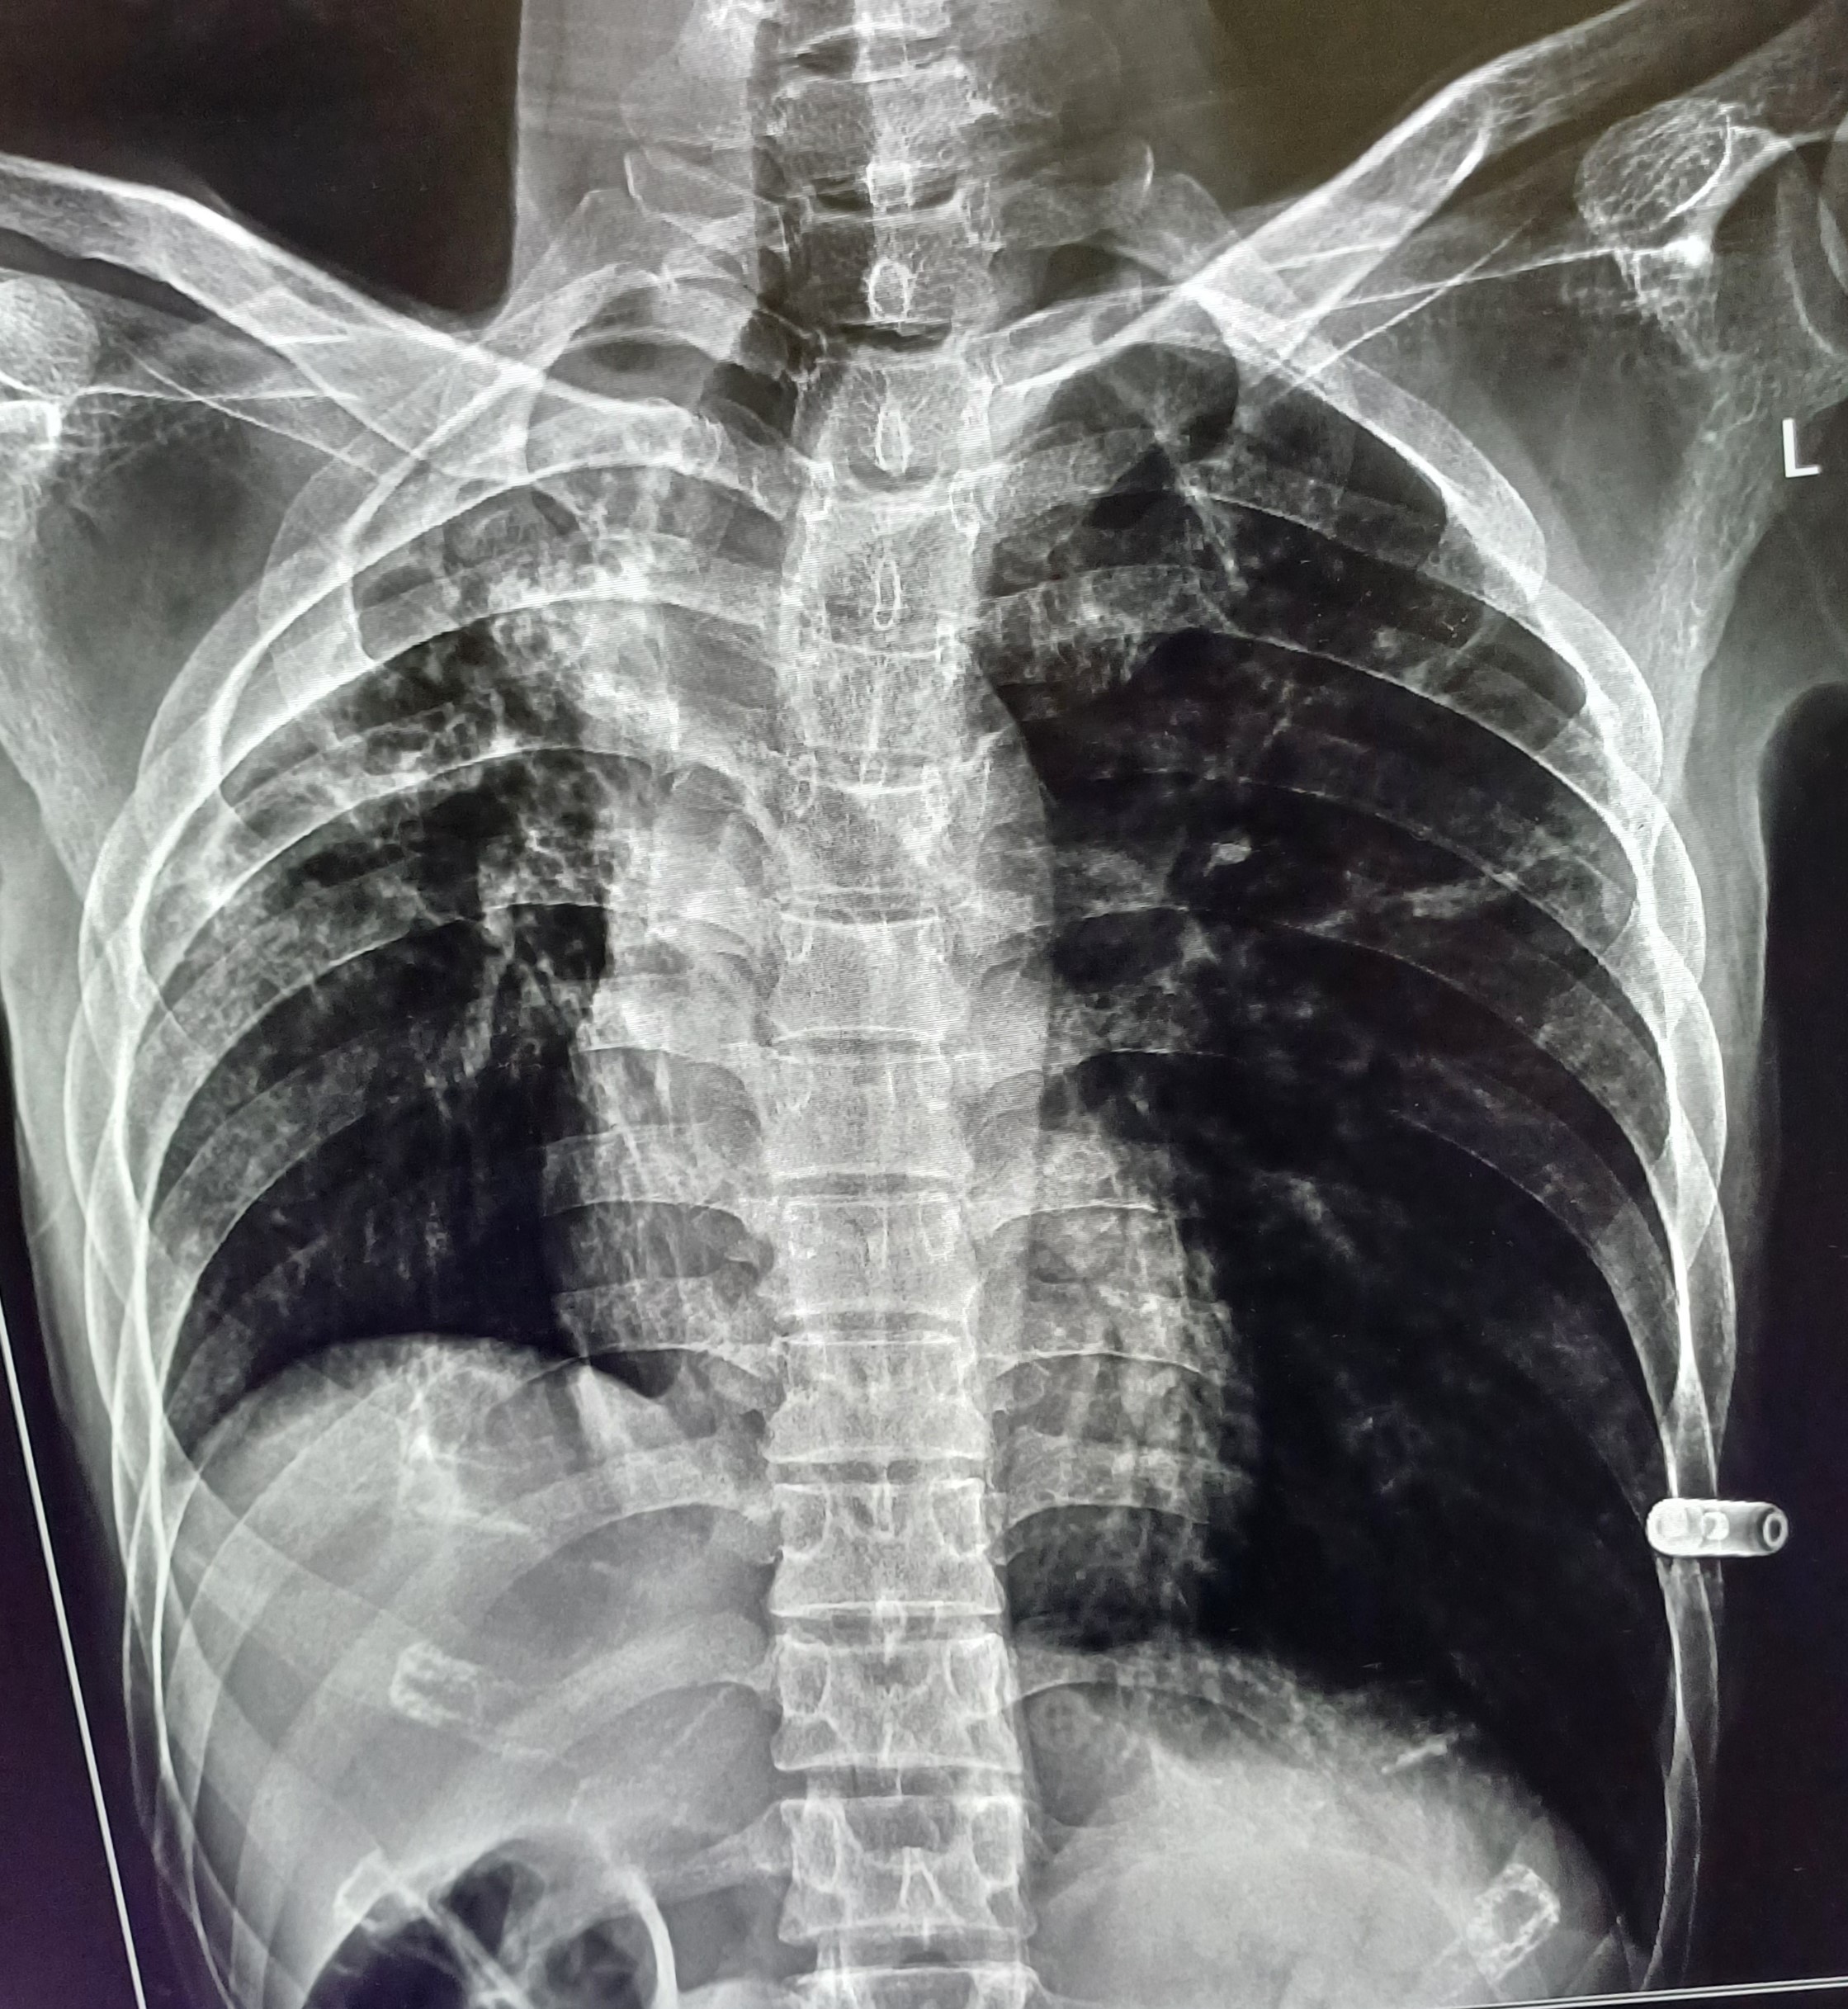

| 52 | IGGMC, Nagpur, Nagpur | P2 | 29-4420 | Hamida Bano | Consent taken on Paper | 56 Yrs. |

Provisional Diag : Post TB Sequelae With Reactivation?

Final Diag : Post TB Sequelae |

Post TB Sequelae | Tracheal Pull Left Side, Left Mid Zone & Upper Zone Fibro cavitary Lesion Present, Compensatory Right lung Hyper Infiltration Present, Few ill-defined Bilateral Lung Opacity Presnt | Abnormality visible on x-ray |